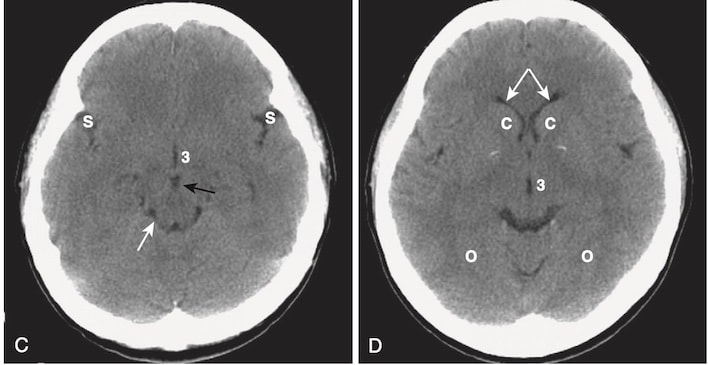

- Nhận biết máu tụ dưới màng cứng cấp tính (Hình 9)

- Trên CT, máu tụ dưới màng cứng cấp tính có hình lưỡi liềm, các dải ngoài não có đậm độ cao có thể băng ngang các đường khớp sọ và vào khe liên bán cầu. Máu tụ không vượt qua đường giữa.

- Điển hình, máu tụ dưới màng cứng lõm vào trong về phía não (máu tụ ngoài màng cứng lồi vào trong) (xem Hình 9, A).

- Sau một thời gian và khi máu tụ chuyển sang bán cấp, hoặc nếu máu dưới màng cứng được trộn với dịch não tủy có độ đậm đặc thấp hơn, chúng có thể biểu hiện đồng tín hiệu/cùng đậm độ (isodense) so với phần còn lại của não, trong trường hợp đó cần tìm các rãnh não bị ép hoặc biến mất hoặc bị đẩy lệch khỏi mặt trong xương sọ như các dấu hiệu của SDH (xem Hình 9, B).

- Các máu tụ dưới màng cứng có thể biểu hiện một mức dịch- dịch sau 1 tuần, khi các tế bào lắng xuống dưới huyết thanh.

- Tụ máu dưới màng cứng mạn tính

- Tụ máu dưới màng cứng mạn tính là những tụ máu xuất hiện hơn 3 tuần sau khi bị chấn thương.

- Máu tụ dưới màng cứng mạn tính thường có đậm độ thấp so với phần còn lại của não (xem Hình 9, C).